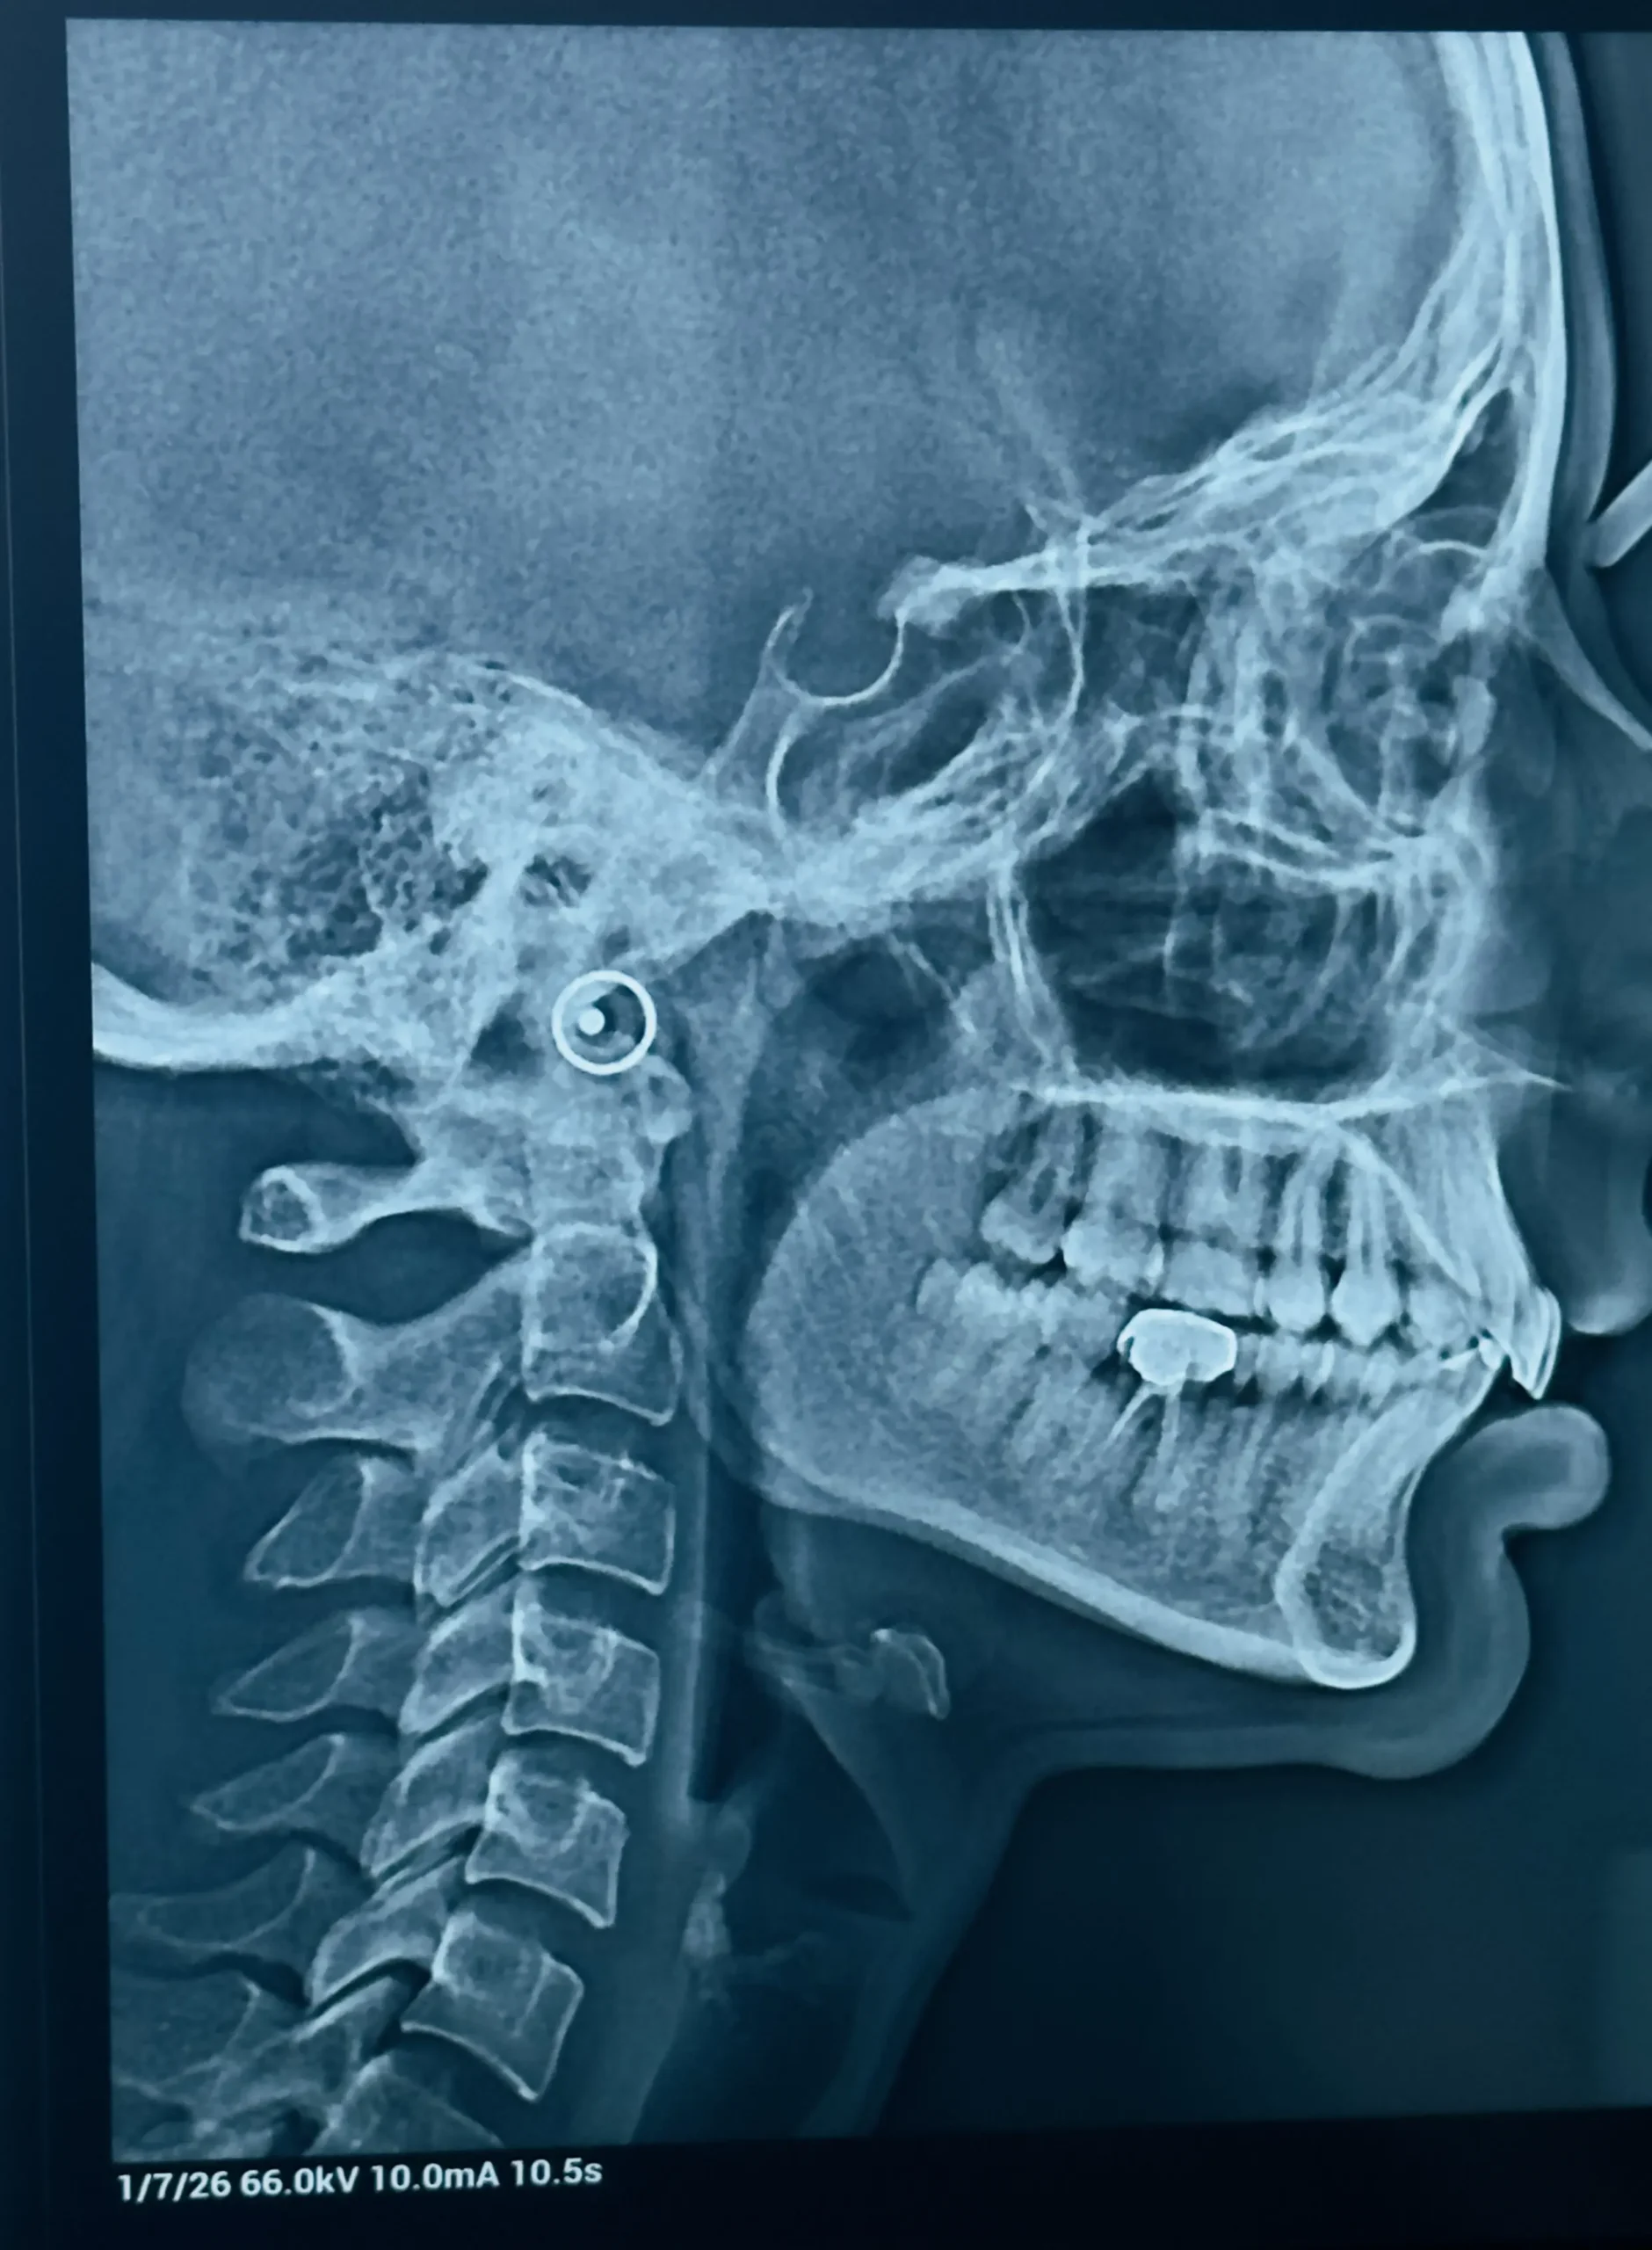

Step 1: Initial Consultation

- Oral examination

- X-rays

- Treatment planning

- Cost estimate